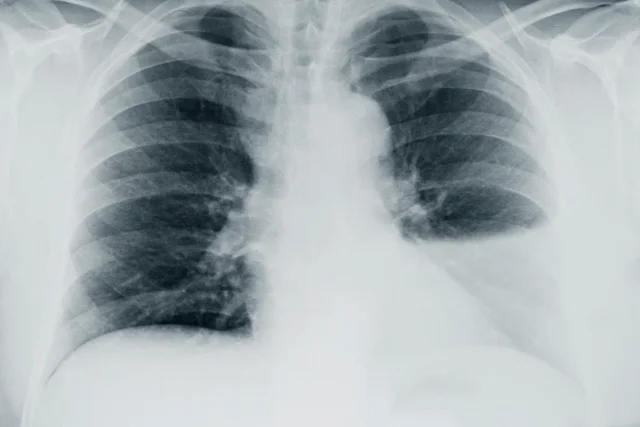

Datos de imagen

Los estudios de imagen útiles en la evaluación de los pacientes con derrame pleural consisten en:

• radiografía de tórax (Postero-Anterior, lateral).

• ultrasonido torácico.

• tomografía computada de tórax.

En pacientes con sospecha clínica de derrame pleural se recomienda realizar inicialmente radiografía de tórax (Postero-Anterior y lateral).

• La sensibilidad de la radiografía de tórax para detectar derrame pleural es 24-100% con especificidad 85-100%

• En casos de derrame pleural mínimo, se solicita una radiografía en posición de decúbito lateral del lado afectado.

• En una radiografía de tórax

• 50 a 75 ml de líquido pleural producen borramiento del ángulo costodiafragmático posterior en la radiografía lateral, (“signo del menisco”).

• 200 ml de líquido pleural producen borramiento de los ángulos cardiofrénico y costodiafragmático.

• La radiografía de tórax lateral puede ayudar a confirmar la presencia de líquido pleural que no se observa en la radiografía postero

anterior.

• Los derrames pleurales pequeños pueden detectarse en una radiografía en posición decúbito lateral sobre el lado afectado